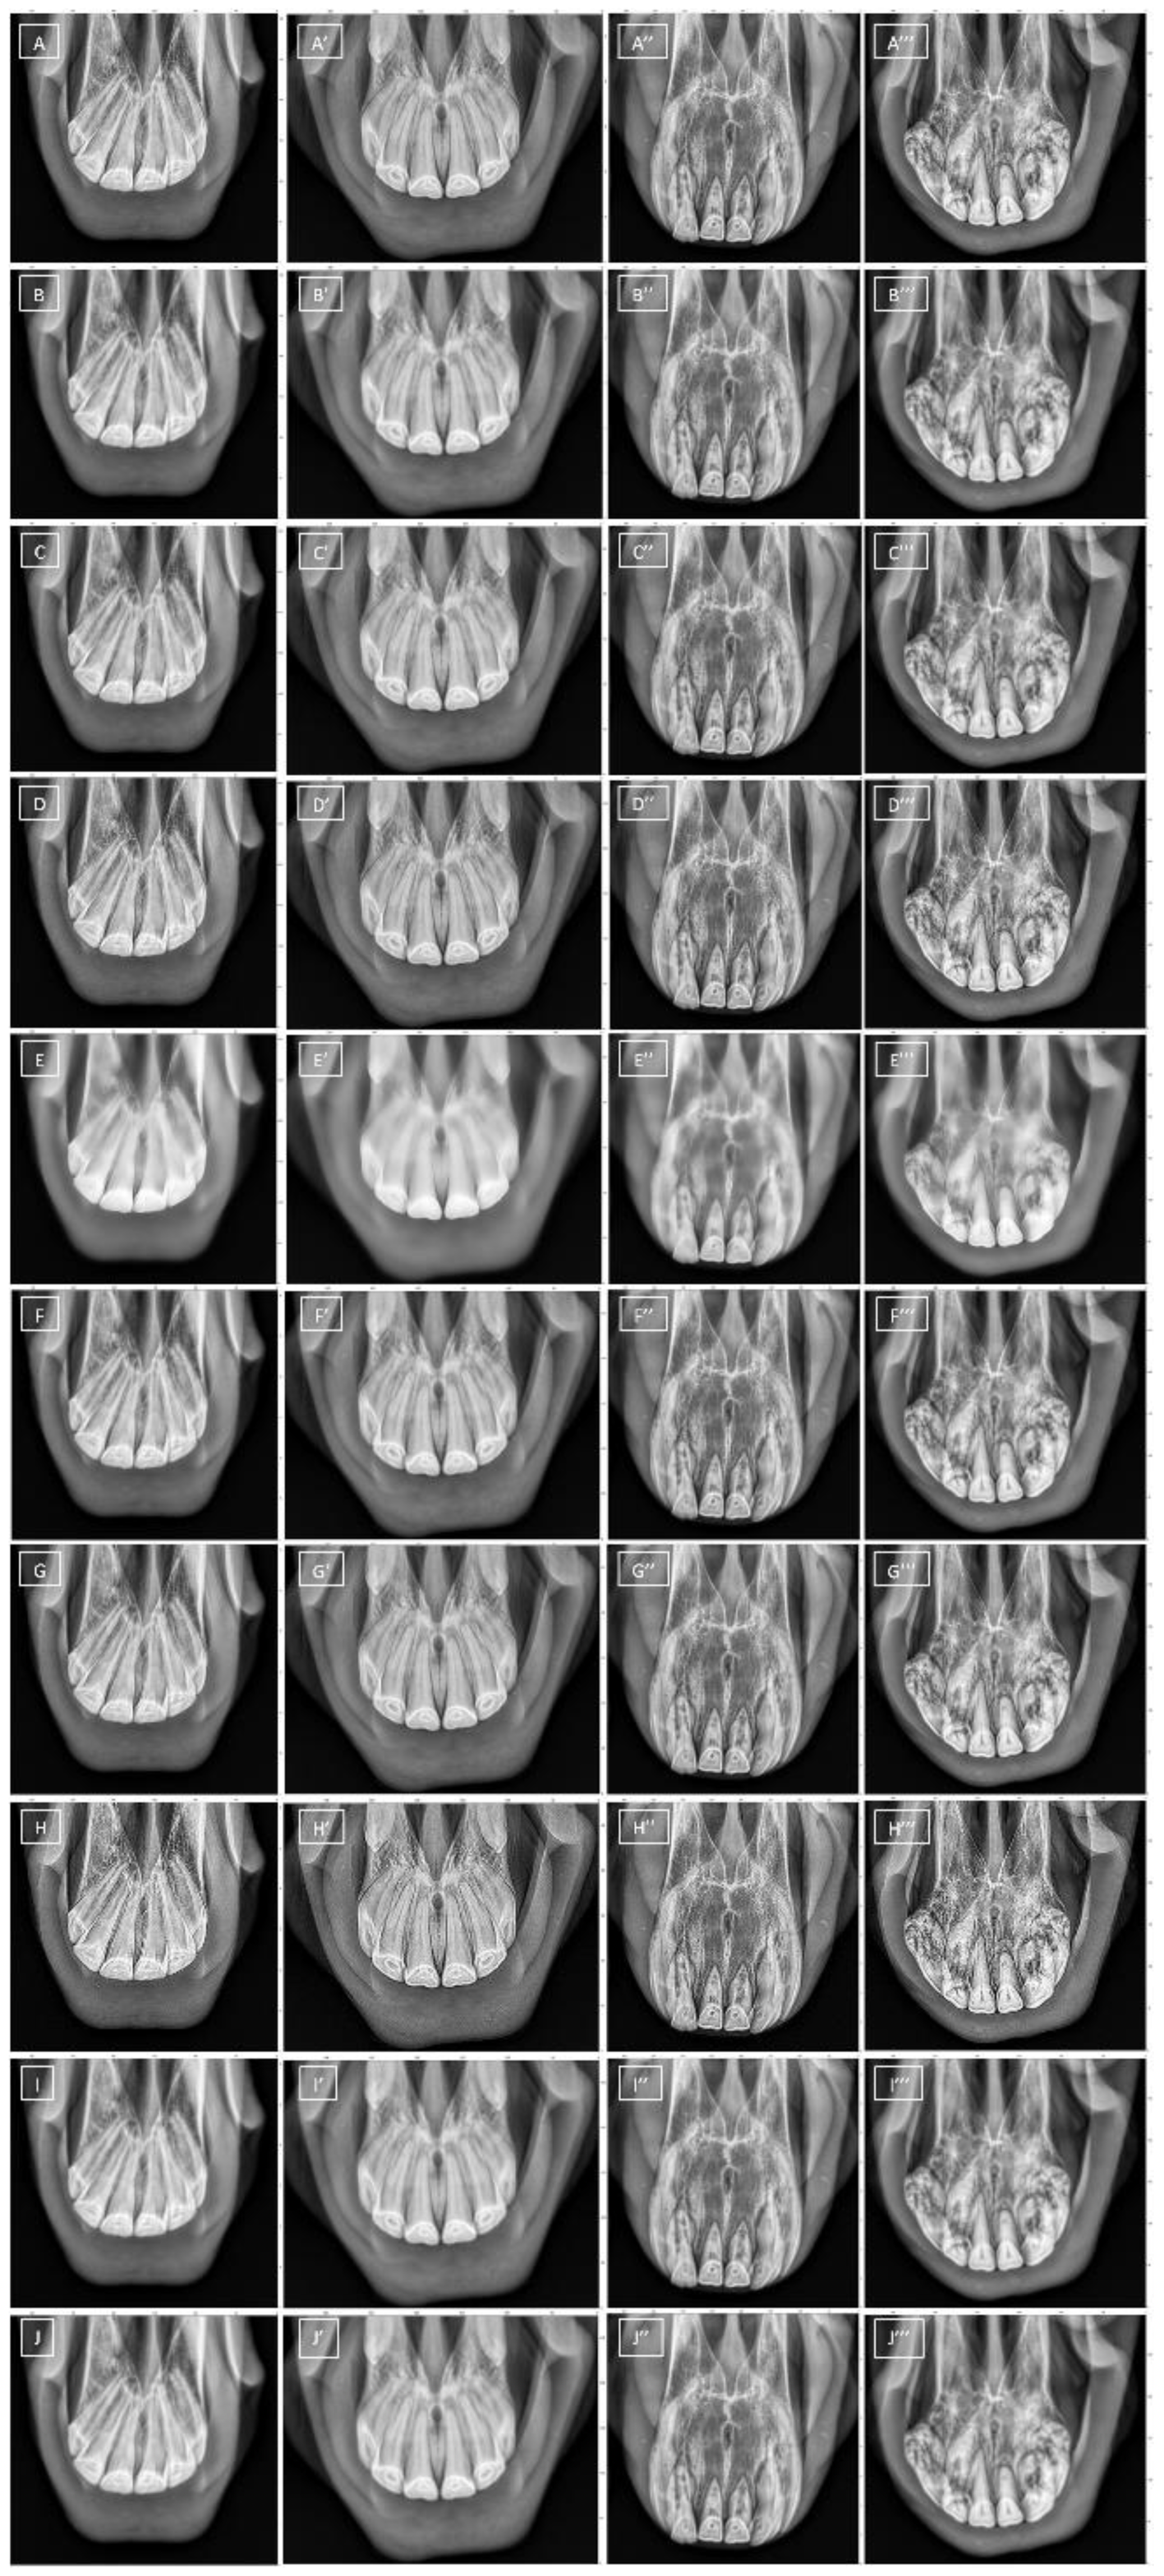

2.2. Image Collection

2.3. Image Processing

2.3.1. Masks Annotation and Image Segmentation

2.3.2. Filtering